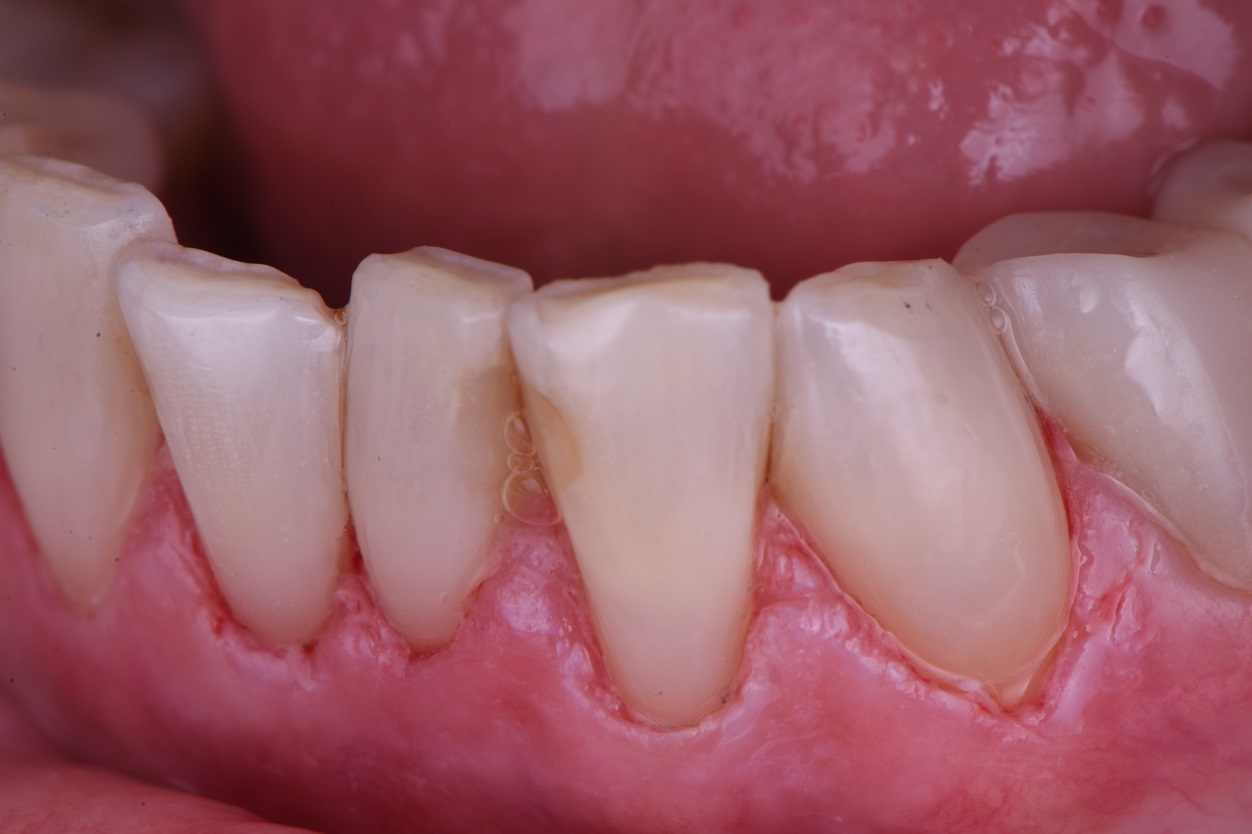

Extensive Class V restorations ahead of freehand direct coronal